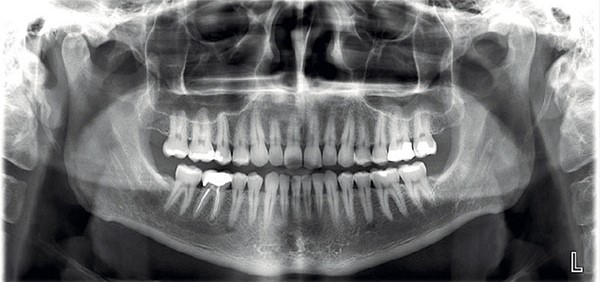

Dental Imaging

img01

Planmeca ProMax 3D

• Low-radiation 3D CBCT scans for safer, more accurate diagnosis of teeth, jaw, and sinus problems.

• Fast and comfortable imaging completed in seconds.

• 3D facial photo with zero radiation to help plan cosmetic and orthodontic treatments more precisely.

• Precise digital models for better-fitting treatments like implants, aligners, and restorations.